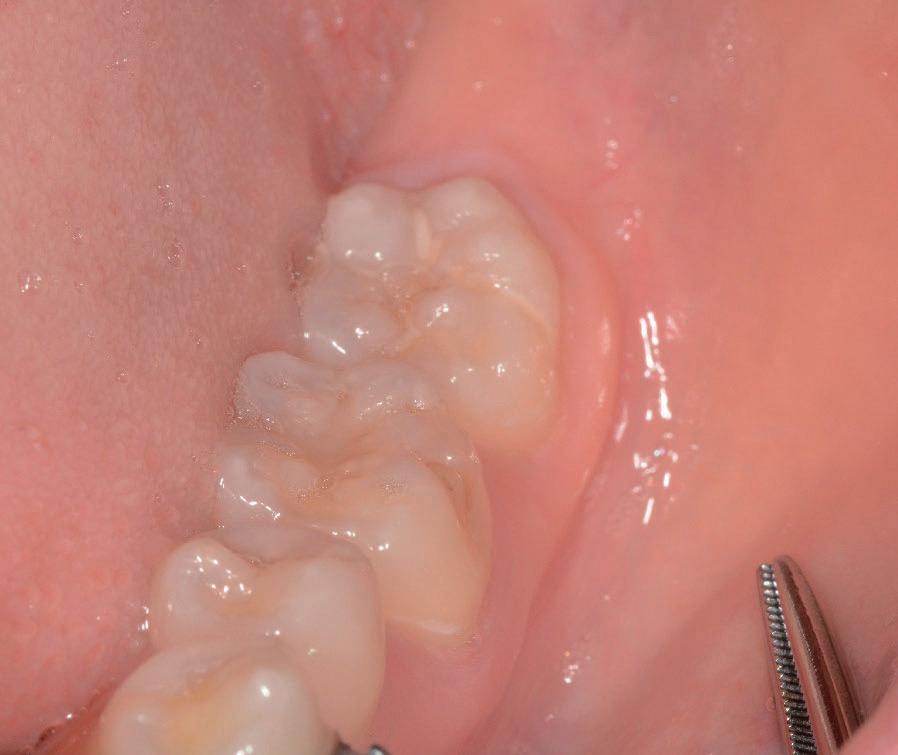

Questo è un paziente di 22 anni ed essendo un amico, ho potuto ben documentare il caso con il suo consenso: il suo dente del giudizio inferiore sinistro è stato estratto utilizzando il manipolo dritto. Figg. 143-149

Figg. 143-149 - Caso 1, paziente di 22 anni: tecnica di estrazione con divisione orizzontale utilizzando il manipolo dritto. Fig. 143 Fig. 144 Fig. 145 Fig. 146 Fig. 147 Fig. 148 Fig. 149